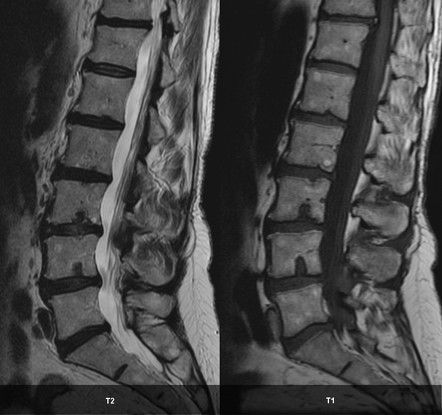

Schmorl’s nodes, also known as intervertebral disc herniations, refers to the protrusion of cartilage of the disc to the adjacent vertebra. Schmorl nodes are a common finding present in people of all ages, however, it is more common in males. The schmorl nodes can be symptomatic or incidental finding. - Acute Schmorl Nodes These are associated with acute back pain thereby indicating inflammation - Chronic Schmorl Nodes These nodes are asymptomatic. There is no association between chronic schmorl nodes and back pain The differential diagnosis of schmorl nodes is: - Spondylodiscitis - Malignancy Reference: https://radiopaedia.org/articles/schmorl-nodes-1